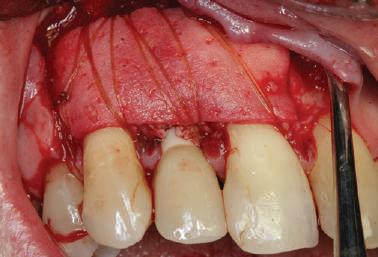

8. La elevarea lamboului cu grosime totală erau evidente dimensiuni adecvate ale crestei alveolare și o calitate osoasă optimă pentru plasarea implantului.

9. S-au observat dimensiuni osoase alveolare adecvate și au fost confirmate densitatea și calitatea osoasă optimă în timpul pregătirii osteotomiei pentru inserarea implantului.

Pacientul s-a întors 4 luni mai târziu pentru inserarea implantului cu vindecarea completă a plăgii (fig. 7). În urma anesteziei locale prin infiltrarea de xilocaină 2% cu adrenalină 1: 100.000, s-a realizat o incizie crestală pe zona edentată pentru a permite elevarea unui lambou cu grosime totală (fig. 8). S-au constatat dimensiuni osoase alveolare adecvate pentru plasarea implantului (fig. 9). Densitatea osoasă optimă și calitatea au fost confirmate în timpul pregătirii osteotomiei pentru plasarea unui implant de 4,2 x 11 mm. A fost înregistrat un cuplu de inserție optim (45 Ncm). S-a conec-